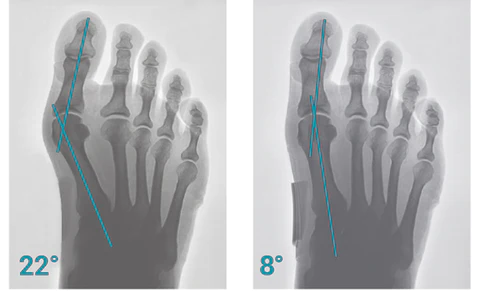

StrongJoints Adjustable Bunion Corrector helps to relieve the pain of the big toe joint and hallux valgus. Repair bunions, hammer toes, overlapping toes. It continuously apply constant pressure to the big toe to realign the toe and slow down the development of the bunion shape, especially when wearing inappropriate or high heels. After wearing a bunion corrector, your bunion pain will disappear completely.

Corrects and Realign Bunion

StrongJoints Adjustable Bunion Corrector are designed to straighten your big toe and return it to its natural position. The strategy behind bunion corrector is that forcing your toe back into its natural position will help it stay there even in the absence of the corrector. It’s adjustable and can be used while resting, sitting, or sleeping. Best use at night while sleeping.